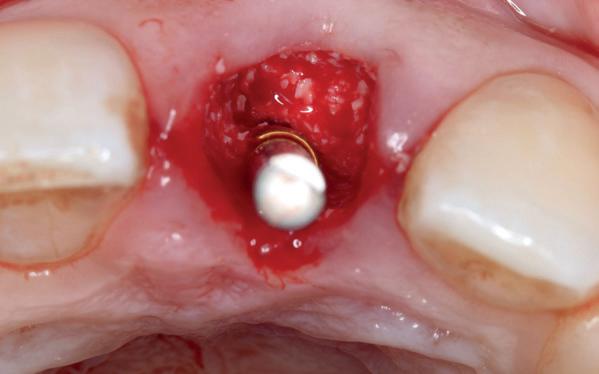

Afbeelding 1 en 2. Een immediate placement (afbeelding 1) is maar weinig invasief en zal weinig nalast geven. Bij een uitgebreide botopbouw (afbeelding 2) daarentegen is de wond veel groter en kan er meer nalast verwacht worden.

In deze casus is extractie van de 37 geïndiceerd in verband met een fistel en restpockets, zoals zichtbaar op de röntgenfoto’s (afbeelding 1). Duidelijk te zien is de forse peri-apicale ontsteking en het botverlies bij de 37, dat zowel richting buccaal als linguaal doorloopt. De 37 wordt atraumatisch verwijderd. Er is aan de linguale zijde veel bot verloren en er is sprake van een perforatie aan de buccale zijde.

Er wordt besloten om botmateriaal te plaatsen in de extractie-alveole. Vervolgens wordt het afgesloten met een titanium versterkt d-PTFE membraan (afbeelding 2). Na vier weken wordt het membraan verwijderd.

Zes maanden na extractie wordt het implantaat 37 geplaatst. Er is sprake van een goede genezing en de processushoogte en -breedte zijn behouden en opgebouwd. Ook is er zichtbaar gekeratiniseerd weefsel

gewonnen. De wond kan na het plaatsen van een healing abutment primair gesloten worden (Afbeelding 3a-3d).